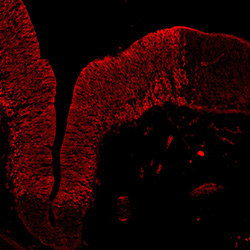

TH

11PCW human midbrain

Merged